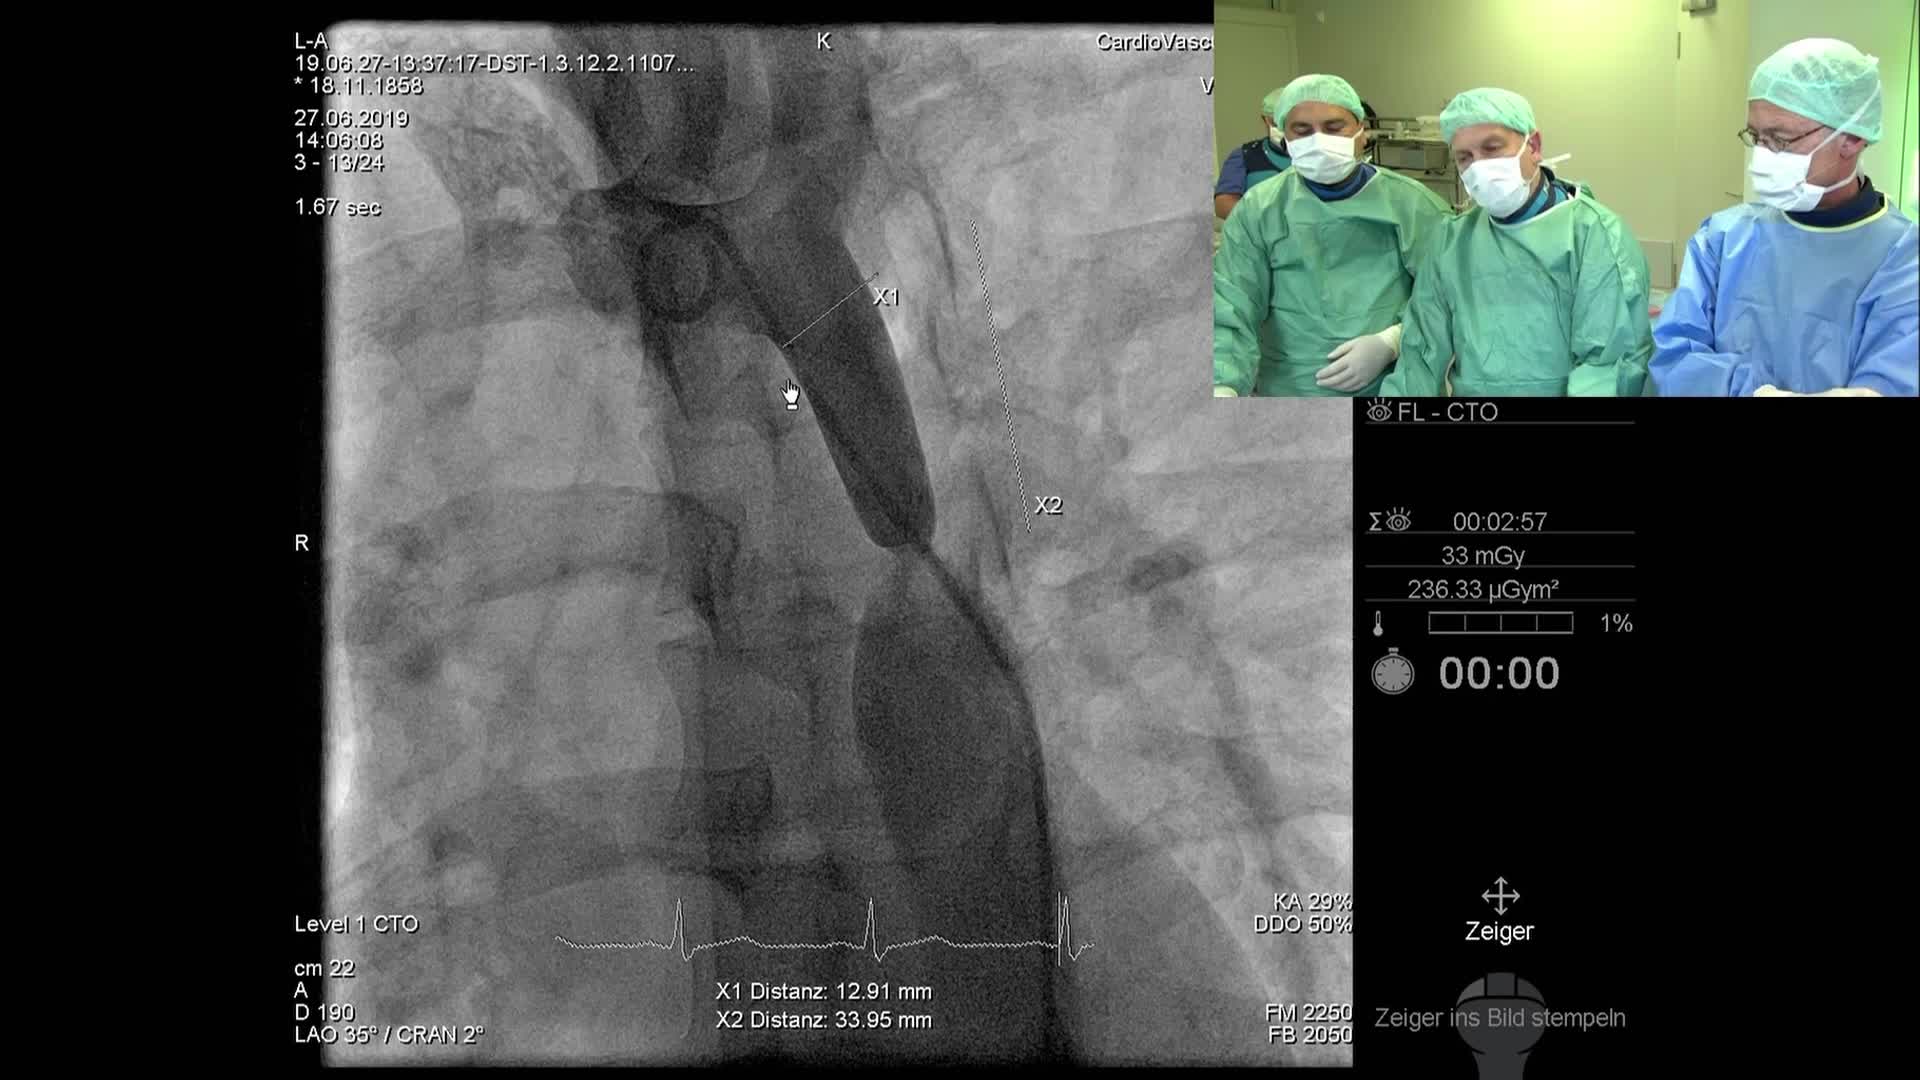

CSI CATHLAB LIVE - VSD CLOSURE WITH THE NEW OCCLUTECH PMVSD OCCLUDER (ANTEGRADE APPROACH)